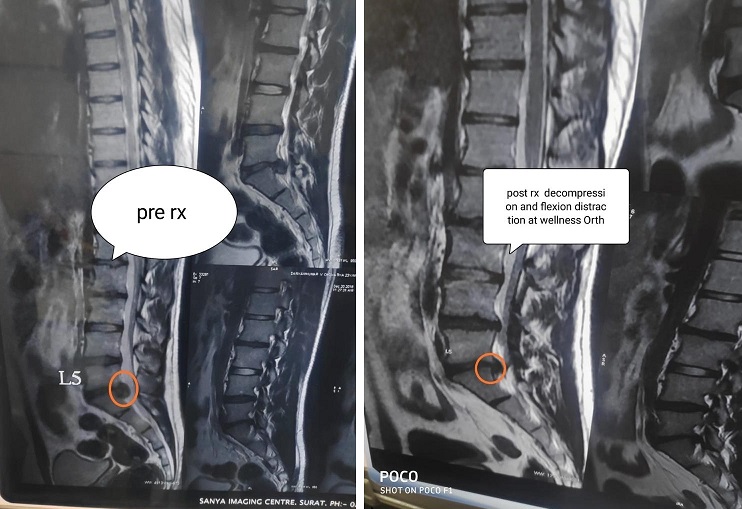

Flexion Distraction

3: Flexion Distraction

Decompression & Flexion Distraction

4: Decompression & Flexion Distraction